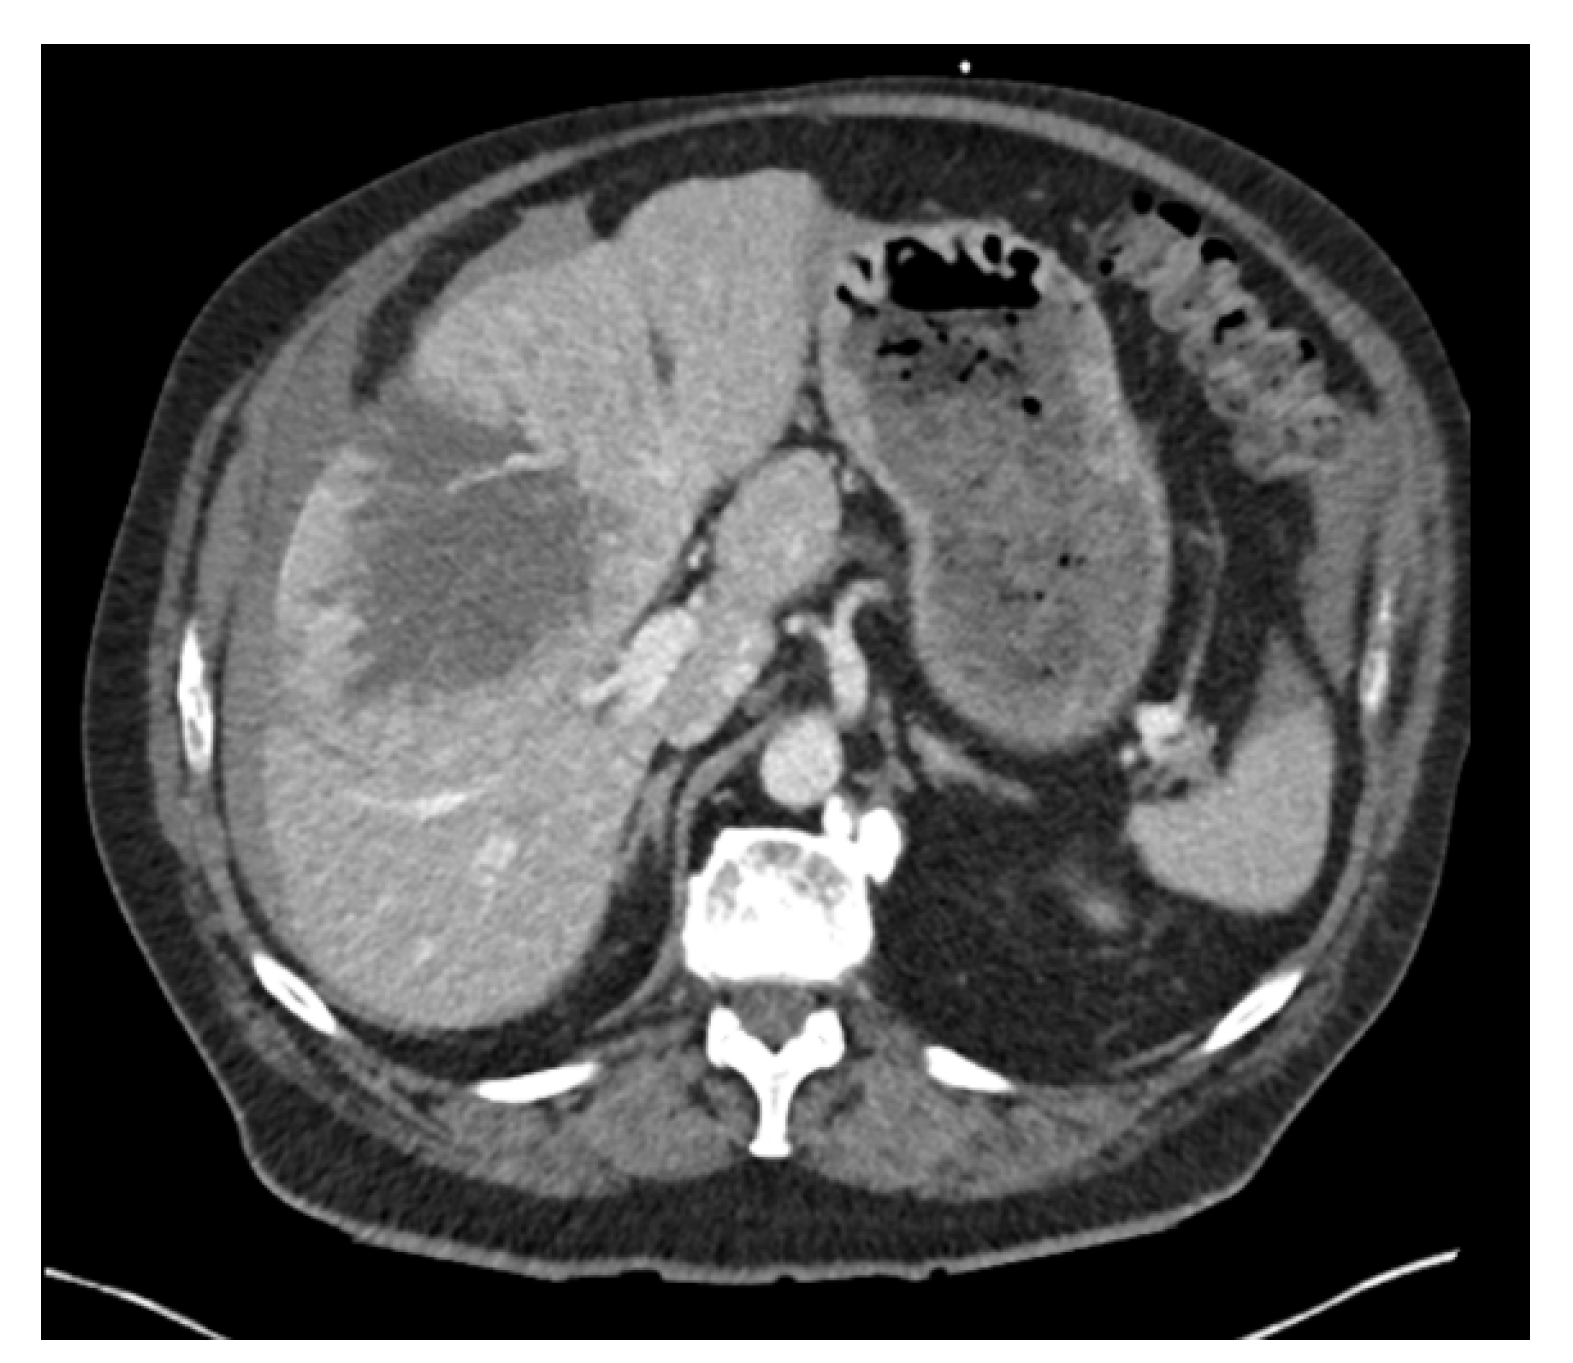

Abdominal Pain Due to Liver Capsule Rupture: A Rare but Fatal Complication of Hepatocellular Carcinoma

2. Case